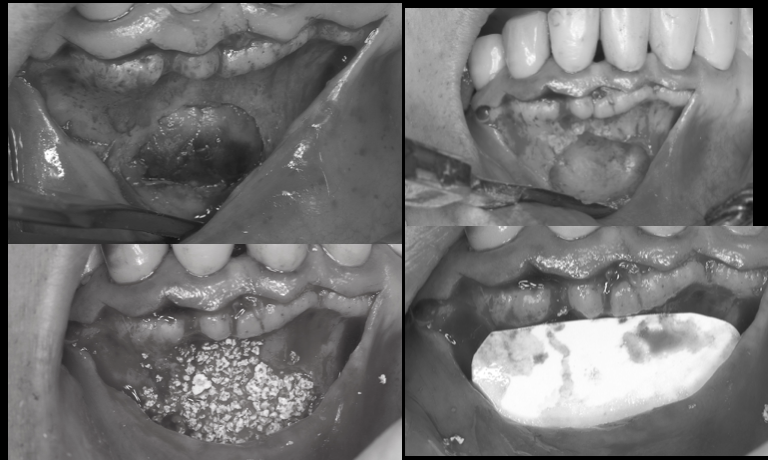

【池袋 歯医者】歯を抜かずに救う“最後の一手”──AT...